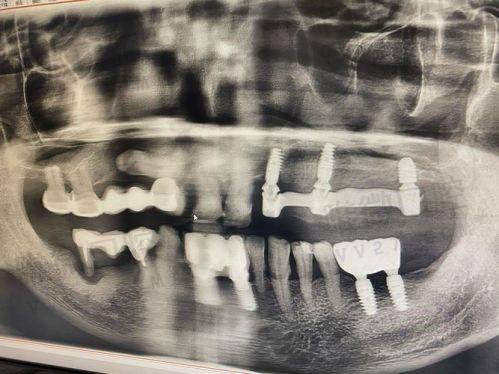

1. 有些人牙槽骨吸收重度,需要做植骨,这就多了1千到3千的费用;

2. 有些人急着修复咀嚼,需要做即刻种植+临时冠,这也意味着服务升级;

3. 不懂区分国产和进口种植体,不同植体价格相差大,即使是韩系两个品牌间也有五六百元差价;

所以,建议在询问时说明自己的口腔情况,并结合拍片结果让医生给出方案,这样预算才会更精细。